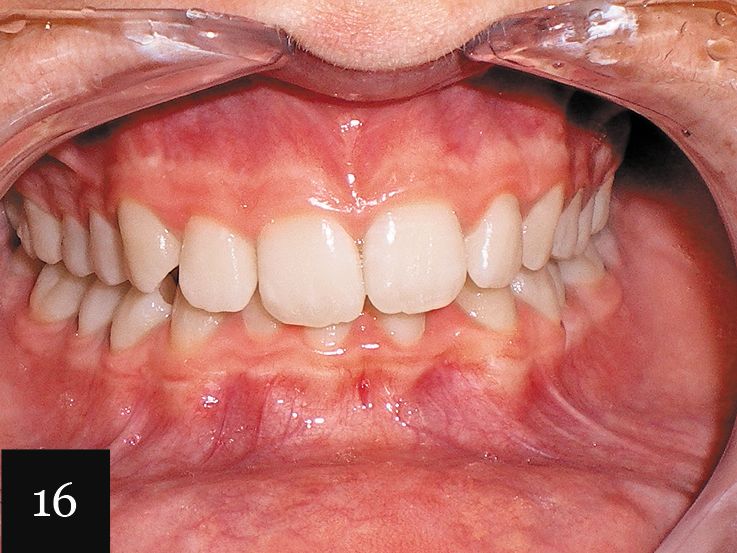

This case was performed on a patient in her late teens who presented with a very deep bite and severe crowding, as seen in Figs. 15-17.

The patient had consulted with multiple dentists who informed her that the lower lateral incisor would have to be extracted and that she was not a candidate for Invisalign. However, with an accurate impression we were indeed able to successfully treat this case with Invisalign, first using a series of 27 aligners, and then following up with an additional impression and eight more aligners for refinement (Figs. 18-20).